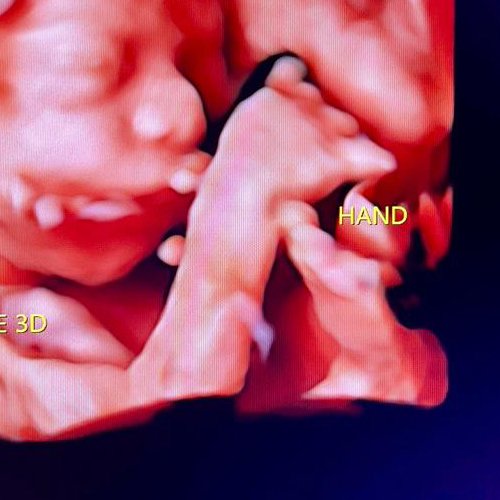

Best Scanning Center In Nakodar